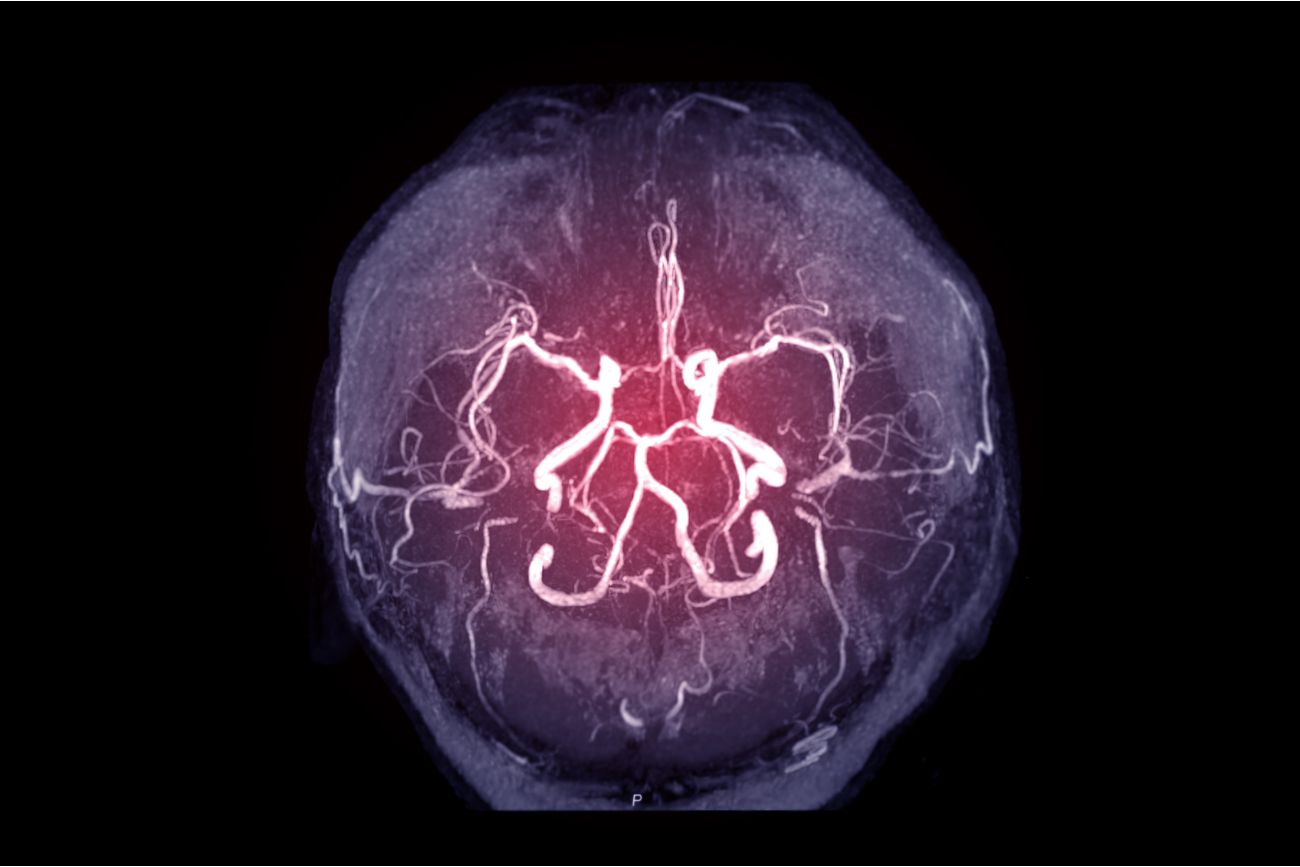

El servicio de Neurocirugía en Sanatorio Allende se encarga del manejo quirúrgico y no quirúrgico de determinadas enfermedades del sistema nervioso central, periférico y vegetativo. Esto incluye sus estructuras de soporte y aporte vascular.

Como tal, la cirugía neurológica abarca el tratamiento quirúrgico y estereotáxico de los pacientes adultos y pediátricos con desórdenes del sistema nervioso, desórdenes del cerebro, meníngeas, base de cráneo y sus vasos sanguíneos. Especialmente se efectúa la cirugía de los pares craneales y espinales a lo largo de su distribución.